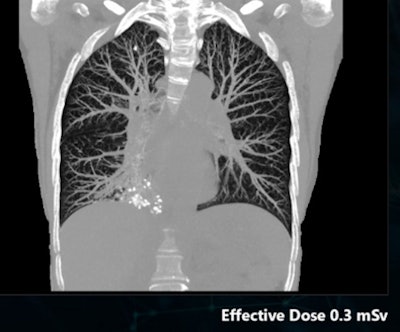

In a similar vein, Canon will demonstrate a technology called SilverBeam that enables extremely low-dose CT lung cancer screening exams to be acquired. SilverBeam is a beam-shaping energy filter that leverages the photon-attenuating properties of silver to remove low-energy photons from the x-ray beam. When combined with AiCE DLR, SilverBeam can enable the acquisition of lung screening exams at a radiation dose in the neighborhood of 0.3 mSv. SilverBeam is pending 510(k) clearance on the Aquilion One/Prism Edition scanner.